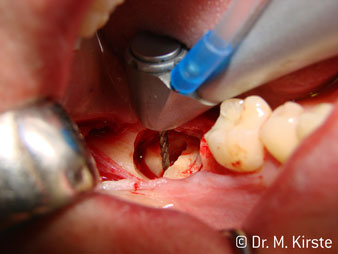

45° ъгъл на наконечника е специално избран поради неговата широка гама от предимства. Колеги, които работят хирургия, и за които този наконечник е главно създаден, скоро ще оценят възможността за ефективна работа в силно ограничени пространства. При екстрахиране на мъдреци, в частност (фиг. 2), няма нужда от голямо разширяване на меката тъкан в областта на бузата (фиг. 3). Дизайнът на главата на наконечника, в съчетание с лекото завъртане на главата по време на препарация, позволява бърза и безопасна работа в ретромоларната област.

Специалният дизайн на лагерите в главата на наконечника гарантира безшумен ход на борера; това прави впечатляващо атравматичен разрез при отделянето на зъба и корена (фиг. 4-9).

Фиг. 3